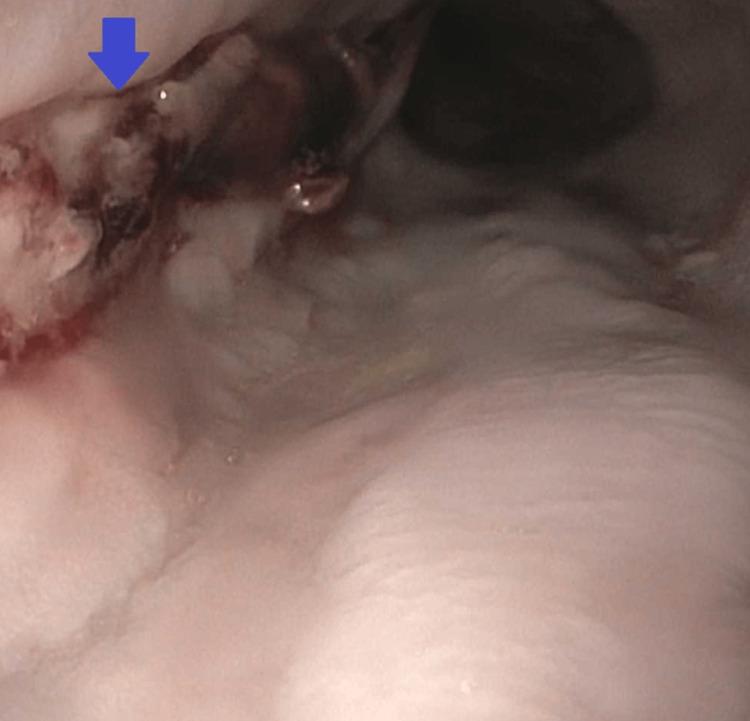

黑色食管:一例罕见的急性食管坏死病例

Acute esophageal necrosis (AEN) also known as necrotizing esophagitis or black esophagus is an extremely rare cause of upper gastrointestinal (GI) bleeding. This condition is considerably rare, and the exact pathophysiology of the development of AEN is still unclear. There is consensus that it is caused by a combination of esophageal mucosal injury due to gastric acid and ischemic injury due to vascular compromise. The management of AEN includes correcting the multitude of underlying predisposing conditions as well as agile symptomatic management and close monitoring for signs of hemodynamic compromise. We here present an interesting case of a middle-aged male patient who presented with hematemesis and underwent emergent esophagogastroduodenoscopy (EGD), which revealed severe necrotic esophagus. We also discussed the risk factors, pathophysiology, and management of AEN.

急性食管坏死(AEN),也称为坏死性食管炎或黑色食管,是上消化道(GI)出血的极其罕见的原因。这种情况相当罕见,AEN发生的确切病理生理学仍不清楚。人们普遍认为,它是由胃酸引起的食管粘膜损伤和血管受损导致的缺血性损伤共同作用所致。AEN的治疗包括纠正多种潜在的诱发因素,以及灵活的对症治疗和密切监测血流动力学不稳定的迹象。我们在此介绍一例有趣的中年男性患者,该患者出现呕血并接受了急诊食管胃十二指肠镜检查(EGD),检查发现食管严重坏死。我们还讨论了AEN的危险因素、病理生理学和治疗方法。